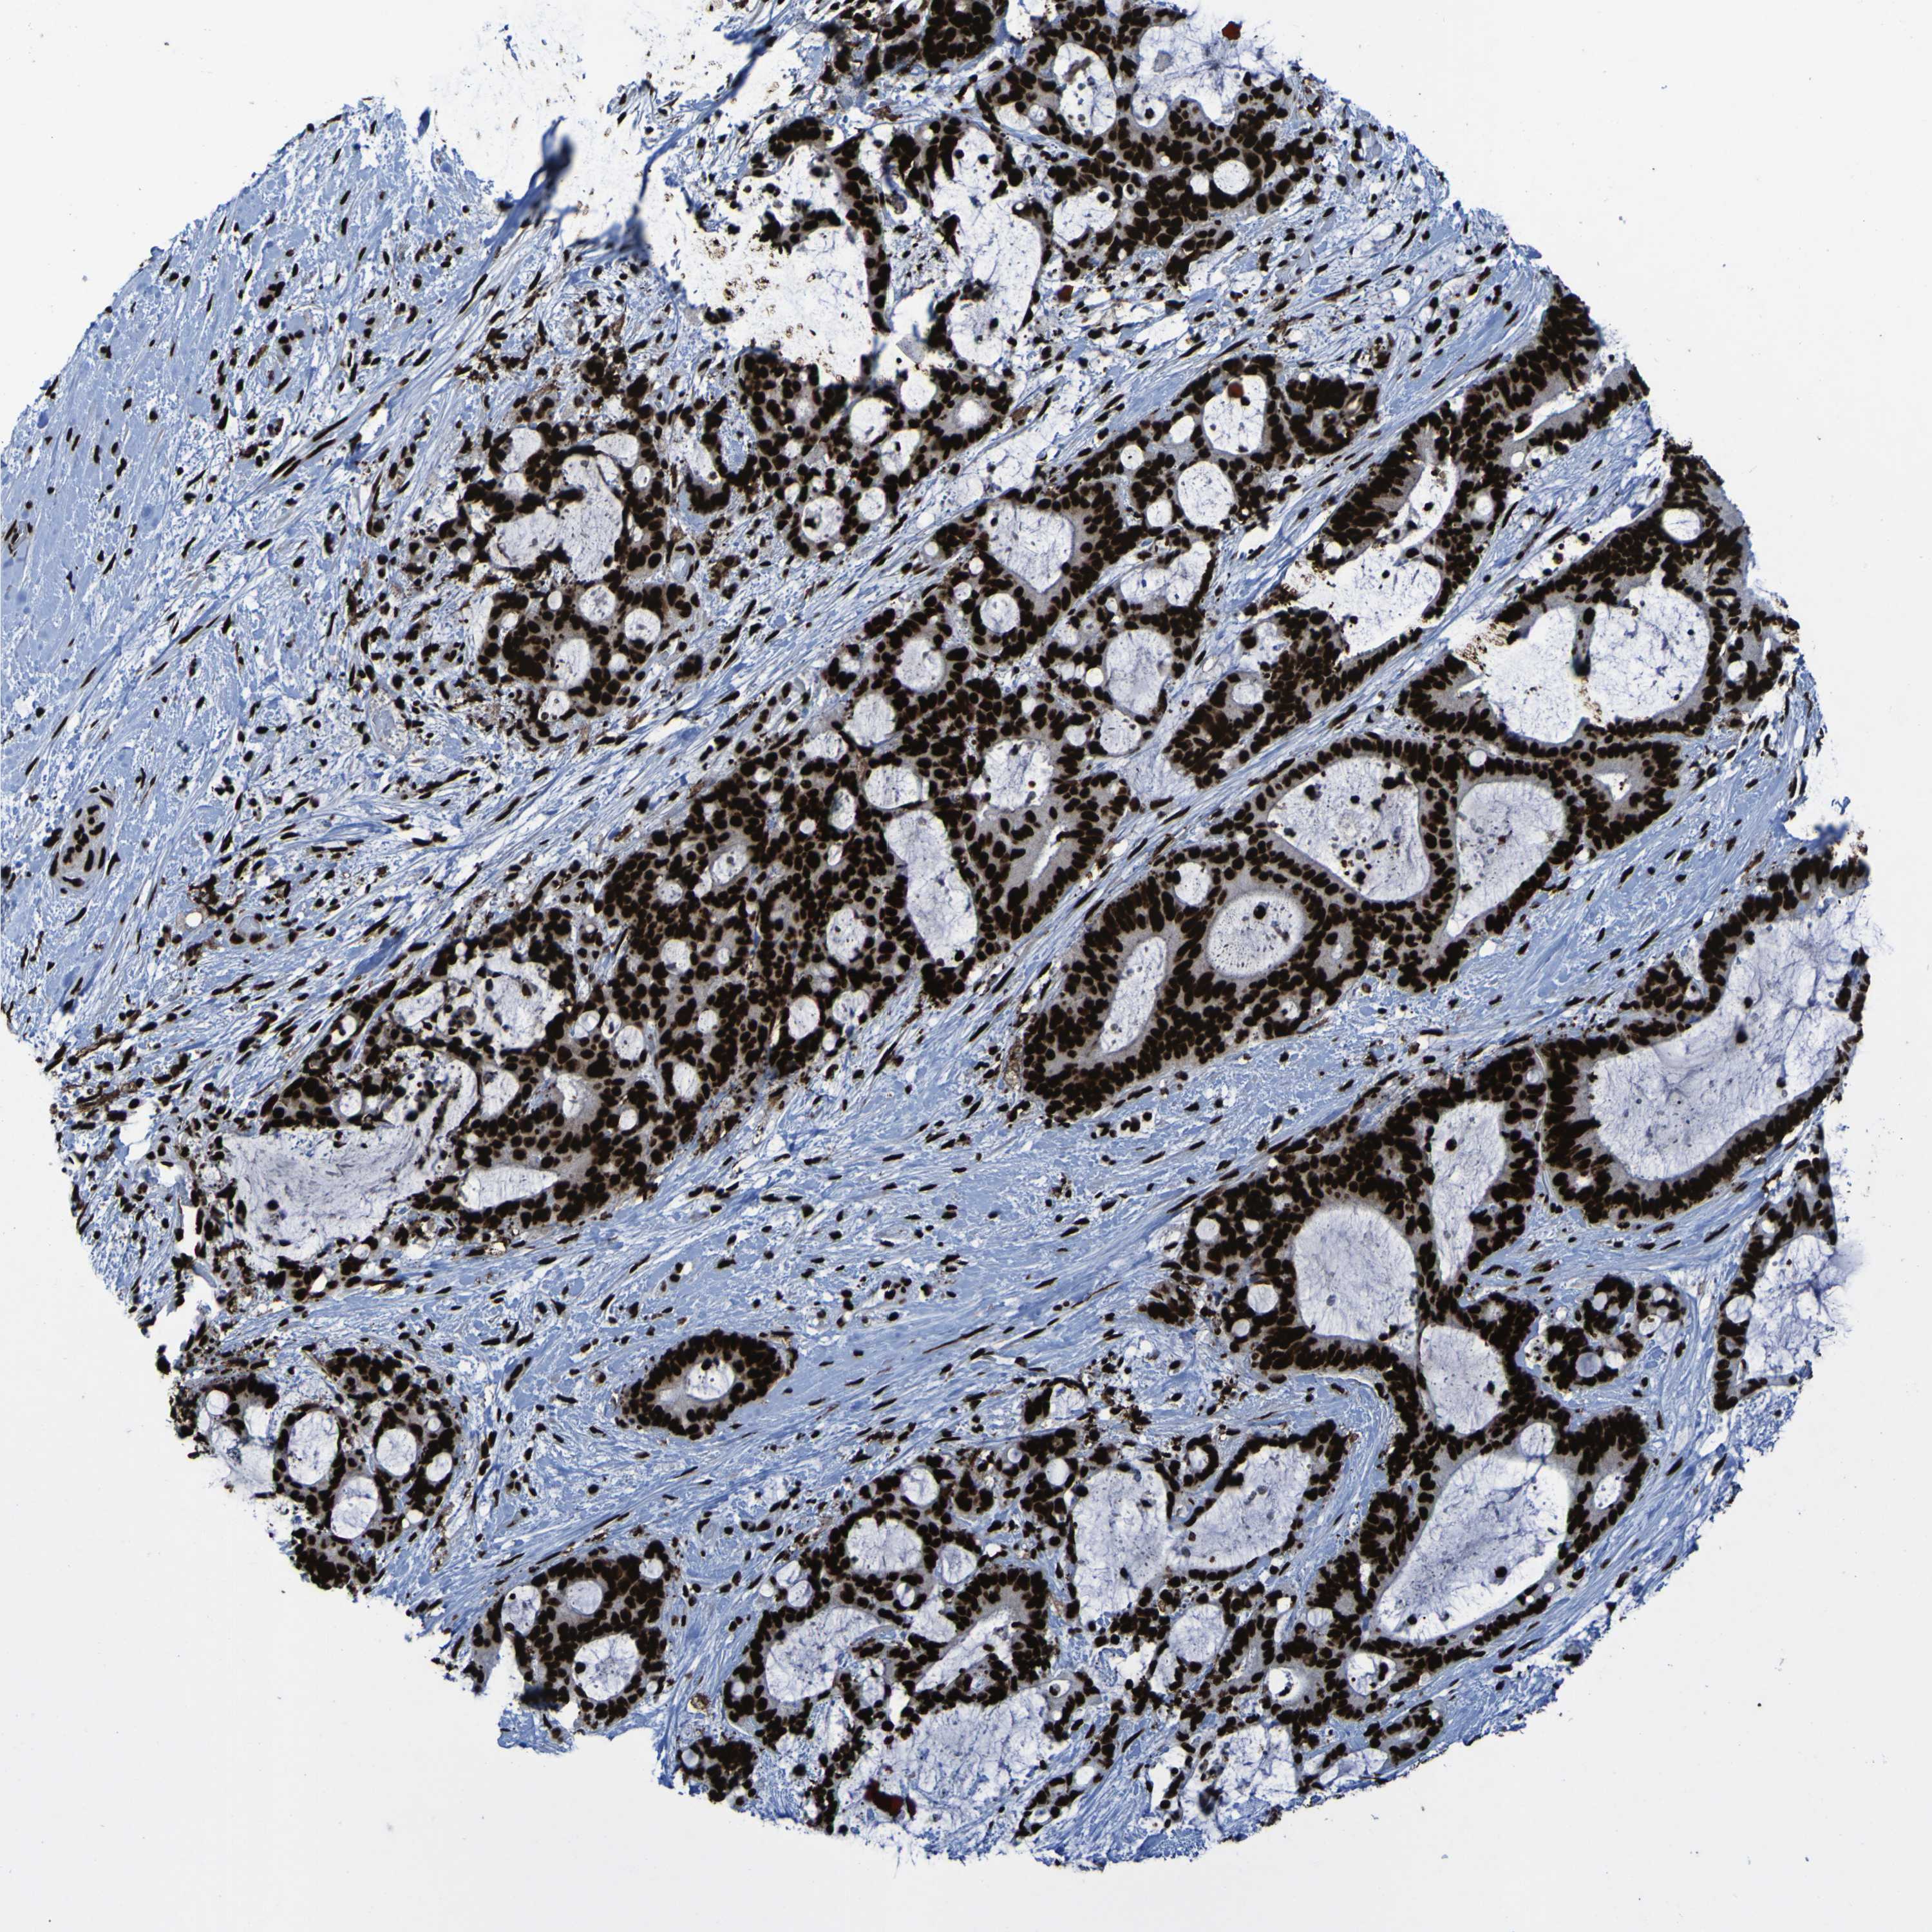

LIVER CANCER - Protein expressioni

A mouse-over function shows sample information and annotation data. Click on an image to view it in a full screen mode. Samples can be filtered based on level of antibody staining by selecting one or several of the following categories: high, medium, low and not detected. The assay and annotation is described here.

Note that samples used for immunohistochemistry by the Human Protein Atlas do not correspond to samples in the TCGA dataset.

Antibody stainingi

Antibody staining in the annotated cell types in the current human tissue is reported as not detected, low, medium, or high, based on conventional immunohistochemistry profiling in selected tissues. This score is based on the combination of the staining intensity and fraction of stained cells.

Each image is clickable and will lead to virtual microscopy that enables deeper exploration of all samples and also displays staining intensity scores, fraction scores and subcellular localization as well as patient and tissue information for each sample.

Antibody HPA011384

Antibody CAB012983

Staining

High

Medium

Low

Not detected

Intensity

Strong

Moderate

Weak

Negative

Quantity

>75%

75%-25%

<25%

None

Location

Nuclear

Cytoplasmic/membranous

Cytoplasmic/membranous,nuclear

Cholangiocarcinoma

Carcinoma, Hepatocellular, NOS